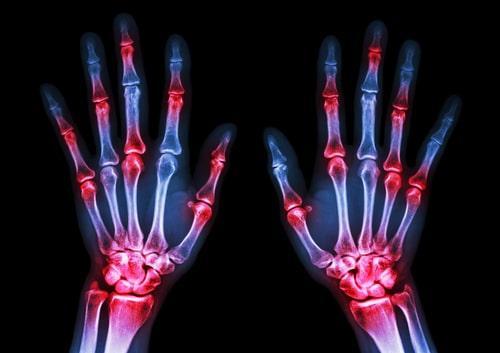

Let's take this recent decision from a federal magistrate judge here in Illinois, Matthew DS v. Saul. In this case, Social Security denied the disability application of a man (the plaintiff) who suffers from “inflammatory arthritis, rheumatoid arthritis, and obesity.” Following a hearing, a Social Security administrative law judge (ALJ) determined these impairments did not qualify the plaintiff for the disability benefits.